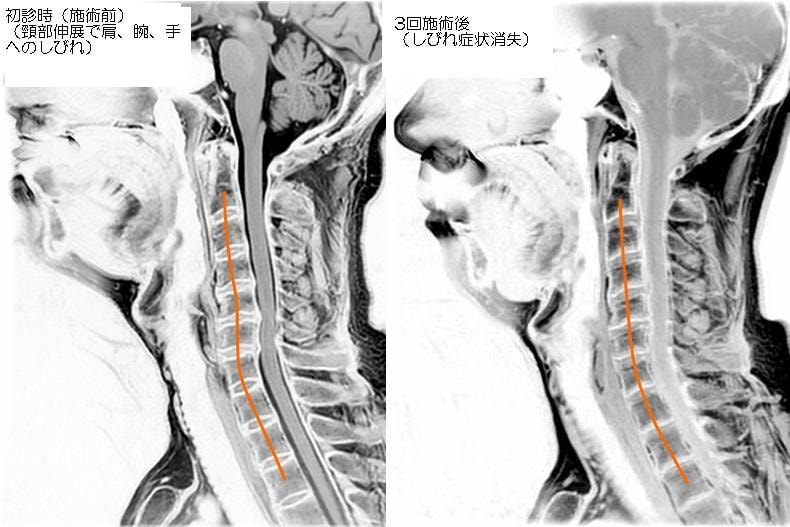

【頸椎ヘルニアの施術例】

・50代男性

・右腕~右手にかけてしびれ、このような症状は初めて

・病院にてMRI検査で頸椎ヘルニアと診断された

初診時にMRI画像を持参して頂いたため、

ヘルニアを発症している箇所を特定できたのが

とても有効だったと思います。

右腕、右手にしびれがある状態でしたが、

3回目施術後には手へのしびれが消失した例です。

実際上記のMRI画像からもヘルニアの症状を

軽減した段階で、頸椎のアライメントも

改善していることが確認できました。